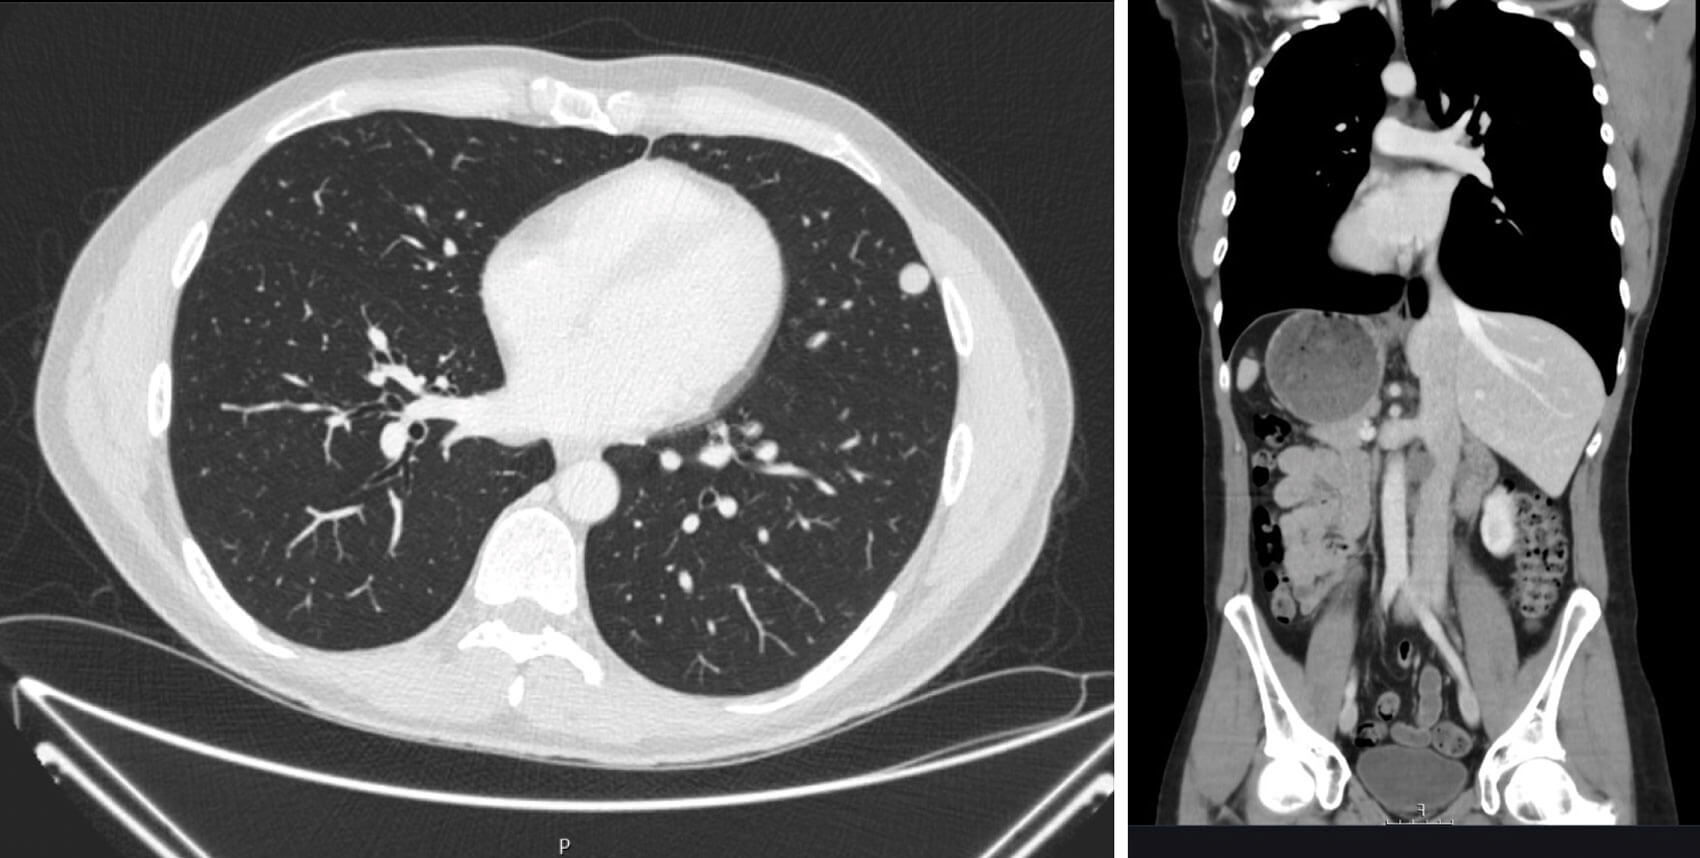

His tumour markers showed a normal AFP and bHCG but he had an elevated LDH of 692. The staging CT chest / abdo / pelvis showed scattered bilateral pulmonary nodules and enlarged aortocaval lymph nodes. These were suspicious for lung metastasis and retroperitoneal lymph node involvement.

Figures 5 and 6: Multiple small lung metastases and retroperitoneal lymphadenopathy.